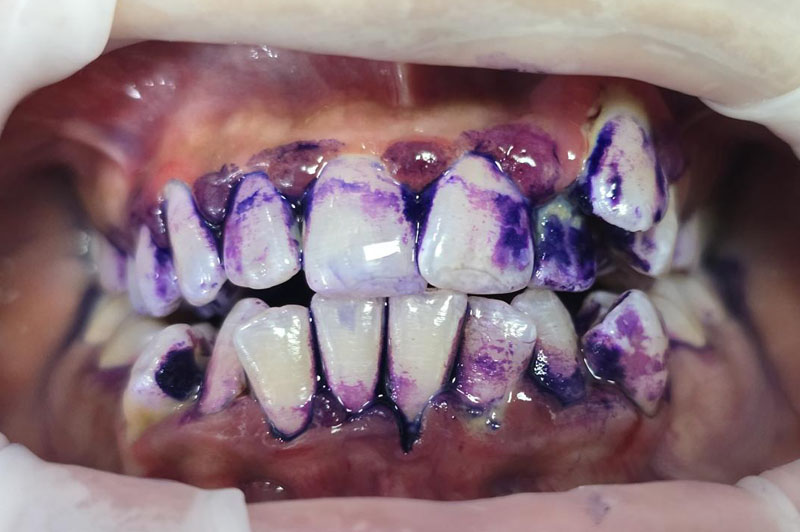

| Technology | Uses advanced Swiss EMS device with guided biofilm visualization and airflow polishing | Manual or ultrasonic scaler with basic polishing |

| Cleaning Precision | Targets biofilm, plaque, and stains on teeth, gums, implants, and braces with digital guidance | Primarily removes surface deposits; may miss hard-to-reach areas |